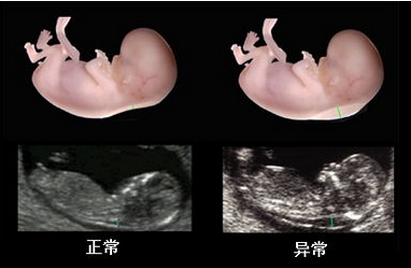

在线咨询系统彩超是筛查胎儿先天缺陷的重要方法,也是每位孕妈妈应该要做的产检项目之一。因此系统彩超的费用就成了孕妈妈们非常关注的问题,不少孕妈妈认为,系统彩超设备是一种先进的仪器,做系统彩超费用一定比较贵。那么,做系统彩超到底多少钱?

贵阳和谐阳光产科借助先进的检测技术,做系统彩超有快速、精准、0痛苦等优势,为就诊孕妇提供更"安全和贴心"的服务。因为在技术和服务上的一体化和人性化,从而备受广大孕妈咪欢迎,许多周边地区的孕妈妈也慕名而来。

贵阳和谐阳光产科拥有经验丰富的超声科医师,擅长胎儿生长发育评估和胎儿畸形的诊断及胎盘病变的超声诊断。与产科医生无缝接力,对系统彩超的检测筛查准确率高,避免了因医院误诊、经验不足等原因导致孕妇流产、胎儿缺陷等问题。